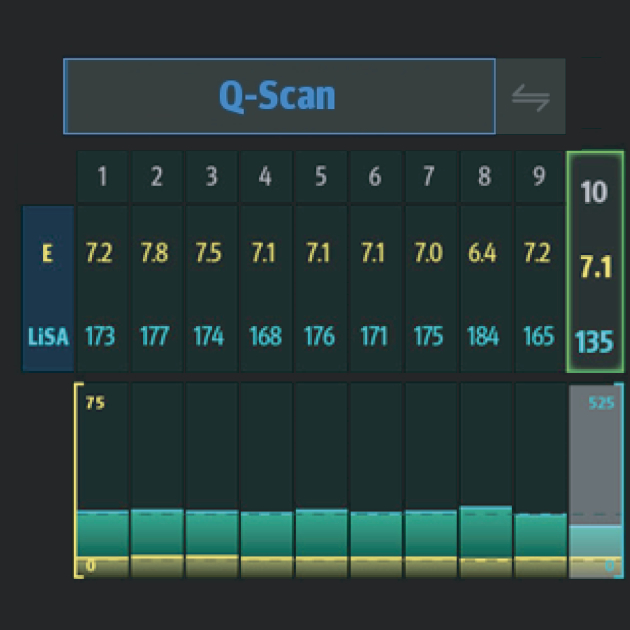

O Hepatus ÃĐ um equipamento de diagnÃģstico profissional n?o invasivo para doen?as hepÃĄticas que fornece resultados quantitativos que indicam o estÃĄgio da fibrose hepÃĄtica. Ele ÃĐ preciso, eficiente, confiÃĄvel e adequado ao acompanhamento de doen?as, abrindo uma nova era para o diagnÃģstico n?o invasivo de doen?as hepÃĄticas.

VÃĄrias solu??es de ultrassom*

â A excelente qualidade de imagem e as fun??es de ultrassom permitem uma avalia??o abrangente da morfologia e hemodin?mica do fÃgado.